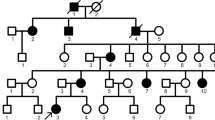

A Chinese family with AI was investigated in this study. This study was approved by the Ethics Committee of the Sichuan Academy of Medical Sciences-Sichuan Provincial People’s Hospital (Chengdu, China). Written informed consent was obtained from all participants or their guardians. Phenotypic characterization and pedigree construction were conducted through medical history taking and clinical and radiographic examinations. Peripheral blood samples were obtained from participants (two affected individuals V:4, III:13 and one nonaffected individual V:5) (Fig. 1i).

Clinical phenotypes and pedigree of the family. a, b Frontal clinical photo and panoramic radiograph of the proband (V:4). c, d Frontal clinical photo and panoramic radiograph of the proband’s father (IV:3). e, f Frontal clinical photo and panoramic radiograph of the proband’s cousin (V:6). g, h Frontal clinical photo and panoramic radiograph of the proband’s cousin (V:7). The V:6 and V:7 are brother and sister. i Pedigree of the family. Males are marked as squares and females as circles. An arrow indicates the proband (V:4), and the black symbols indicate the affected individuals

We identified a five-generation Chinese family with AI phenotype when the proband (V:4, Fig. 1i), a 27-year-old female, presented to the Sichuan Academy of Medical Sciences-Sichuan Provincial People’s Hospital (Chengdu, China) with complaints of unsightly teeth. Her pedigree contained 59 family members, 26 of whom were affected by AI according to our research. Clinical examination of affected individuals revealed that the different severity of enamel defected affected the deciduous and permanent teeth. No symptoms were observed in the individuals, other than the dental phenotype.

The proband (V:4) inherited enamel defects from her father. The teeth of the proband exhibited yellowish colouration and rough surfaces with plaque accumulation. The enamel had obvious attrition, exposing dentin (Fig. 1a). The panoramic radiograph of the proband showed that the enamel density was reduced and could not be distinguished from dentin (Fig. 1b). Clinical examination of proband’s father (IV:3) showed similar clinical symptoms (Fig. 1c). Besides these symptoms, clinical features of proband’s cousin (V:7) included anterior cross bite (Fig. 1g).